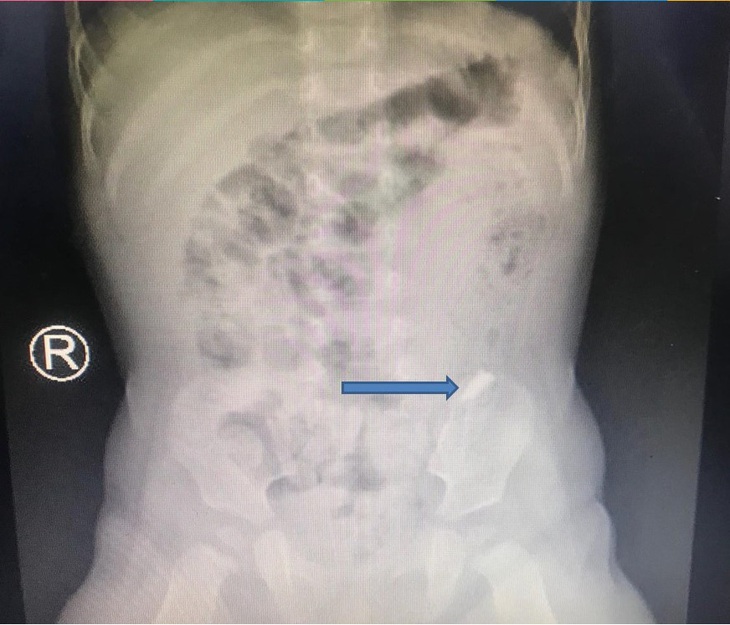

Dị vật là miếng kiếng vỡ có kích thước 0,3x1cm di chuyển trong đường tiêu hóa bé trai 10 tháng tuổi - Ảnh: Bệnh viện cung cấp

Kết quả X-quang thấy dị vật đi nhanh qua thực quản, dạ dày, môn vị, xuống tá tràng… Các bác sĩ đánh giá việc nội soi gắp dị vật khá khó khăn vì nguy cơ gây chảy máu, thủng ruột, dạ dày, thực quản…

Bệnh nhi được các bác sĩ cho sử dụng các loại thuốc băng dạ dày, thuốc làm mềm phân, tạo điều kiện cho trẻ đi ngoài ra dị vật. Kết quả sau gần 2 ngày theo dõi, bé Đ. đã đi ra được mảnh kiếng 0,3x1cm.